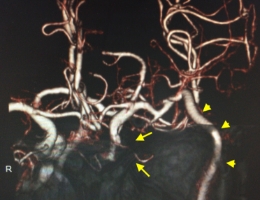

治療前

治療後

物が二重に見えるようになって発症した内頚動脈大型動脈瘤(矢印)の症例です。クリッピング術で直接動脈瘤をつぶすことができないため、バイパス術(矢印)を増設し内頚動脈を遮断することで動脈瘤を治療しました。